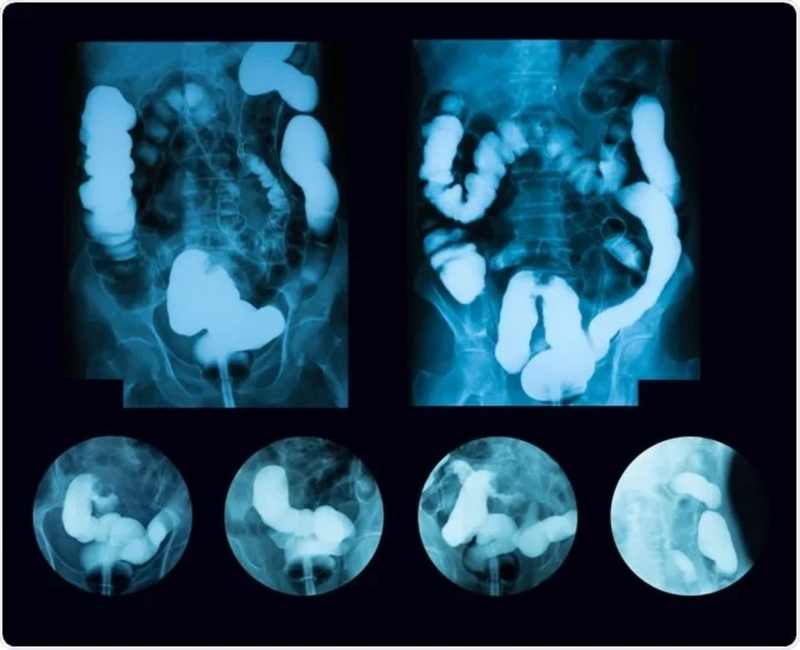

Chụp X - quang đường tiêu hóa giúp bác sĩ đánh giá, theo dõi, chẩn đoán các tổn thương, bệnh lý bên trong đường tiêu hóa. Kỹ thuật này gồm có chụp X quang đường tiêu hóa trên (thực quản - dạ dày) và chụp X quang đường tiêu hóa dưới (khung đại tràng).

Chụp X quang đại tràng dùng thuốc cản quang thường được bác sĩ chỉ định trong trường hợp cần chẩn đoán các bệnh lý về đại tràng, trong đó có ung thư đại tràng. Hiện nay, có hai kỹ thuật chụp đại tràng là dùng cản quang đơn và cản quang kép để bộc lộ rõ các tổn thương ở niêm mạc đại tràng, tổn thương trong thành đại tràng và tổn thương đè ép từ bên ngoài đại tràng.

Chụp X quang đại tràng cản quang đơn thường dùng để đánh giá các tình trạng như: Tắc đại tràng, rò đại tràng, bệnh nhân là người yếu sức, người già, người bệnh nặng. Chụp X quang cản quang kép thường được chỉ định khi cần phát hiện bệnh viêm ruột, cần đánh giá trực tràng một cách chi tiết hay cần phát hiện các tổn thương nhỏ dưới 1cm.